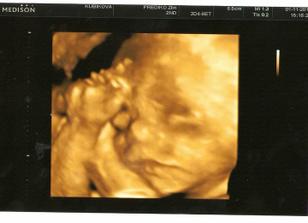

1.11. 3D ultrazvuk 🙂